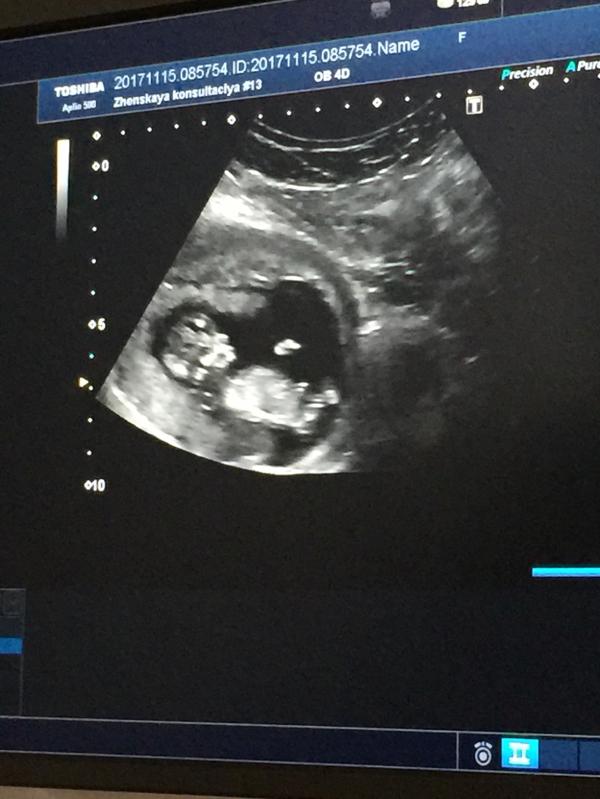

Я расстроена ( ходила на скрининг и на УЗИ мне сообщили , что плацента расположена слишком низко , тяжелое поднимать нельзя😖а как не поднимать , моя ещё маленькая совсем и не ходит сама , хочешь не хочешь , в коляску , за столик , на кровать , переодеть , вот и тягаешь туда обратно ! Живот тянет постоянно , хз из-за чего , может тонус , а может из-за того что плацента низко ! Вообще низкая плаценты это опасно ?